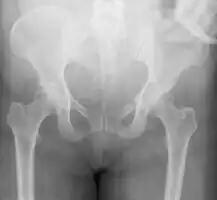

A pelvic fracture is a break of the bony structure of the pelvis.[1] This includes any break of the sacrum, hip bones (ischium, pubis, ilium), or tailbone.[1] Symptoms include pain, particularly with movement.[1] Complications may include internal bleeding, injury to the bladder, or vaginal trauma.[2][3]

Common causes include falls, motor vehicle collisions, a vehicle hitting a pedestrian, or a direct crush injury.[2] In younger people significant trauma is typically required while in older people less significant trauma can result in a fracture.[1] They are divided into two types: stable and unstable.[1] Unstable fractures are further divided into anterior posterior compression, lateral compression, vertical shear, and combined mechanism fractures.[2][1] Diagnosis is suspected based on symptoms and examination with confirmation by X-rays or CT scan.[1] If a person is fully awake and has no pain of the pelvis medical imaging is not needed.[2]